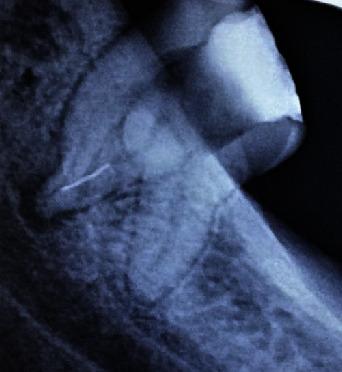

The success of endodontic therapy is attributed to complete arbitration of the bound entities concealed within the complexity and absolute disinfection of the root canal system, thus, deeming it mandatory to effectively negotiate and overcome the challenges posed by obstruction, either iatrogenic or anatomic. To achieve this, considerable depth of knowledge and expertise with reference to variations in root canal morphology and clinical mishap management is substantially as important as developing fine observation skills in conjunction with an appropriate armamentarium and a keen sense of determination, thereby enhancing one's clinical acumen by several folds. In the present case, following rubber dam isolation, the temporary restoration was removed, and the remaining carious dentin was excavated. Endodontic access cavity was refined and explored with a DG-16 probe, following which three separate canal orifices were identified in the pulp chamber floor (mesiobuccal, mesiolingual, and distal). On further observation under a surgical operating microscope and continuous exploration with the DG-16 probe, a fourth canal was found in the mesial aspect of the tooth (middle mesial). With instrumentation, it was confirmed that a fractured object was indeed present at the apical third of the mesiolingual root of tooth 38. Bypassing of the fractured fragment was initiated with a size 10 SS K-file coupled with copious irrigation with 3% sodium hypochlorite. In the present case report, four distinct canals comprising 3 mesial and 1 distal canal were recognized, and the fractured instrument in one of the canals was bypassed successfully.

根管治疗的成功归因于对隐藏在根管系统复杂性中的相关实体进行彻底清理以及对根管系统进行彻底消毒,因此,必须有效应对并克服由医源性或解剖学原因造成的阻塞所带来的挑战。要做到这一点,对根管形态变异和临床失误处理方面有相当深入的知识和专业技能,与培养敏锐的观察技巧、配备合适的器械以及坚定的决心同样重要,从而使临床敏锐度提升数倍。在本病例中,在橡皮障隔离后,去除了临时修复体,并挖除了剩余的龋坏牙本质。用DG - 16探针修整并探查根管入口洞形,随后在髓室底发现了三个独立的根管口(近中颊侧、近中舌侧和远中)。在手术显微镜下进一步观察并继续用DG - 16探针探查时,在牙齿的近中面(近中中部)发现了第四条根管。通过器械操作,证实38号牙近中舌根根尖三分之一处确实存在一个折断的物体。先用10号不锈钢K锉绕过折断碎片,并辅以大量3%次氯酸钠冲洗。在本病例报告中,识别出了四条不同的根管,包括3条近中根管和1条远中根管,并且成功绕过了其中一条根管内的折断器械。